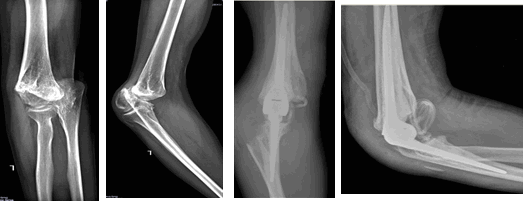

В 141 случае к нам обращались пациенты с внутрисуставными переломами дистальной трети плечевой и (или) проксимальной трети локтевой кости. Оперативное лечение в объеме эндопротезирования было выполнено в плановом порядке, после предварительного обследования. Во всех случаях данной группы оперативное лечение в объеме реконструкции и накостного остеосинтеза не представлялось перспективным ввиду обширности травмы костной структуры и незначительной величины костных фрагментов. Интраоперационно были удалены все нежизнеспособные костные фрагменты, после чего выполнялось стандартное первичное эндопротезирование локтевого сустава. Объем движений в локтевом суставе по Марксу составлял 5-0-150. Учитывая сохранность стереотипа движений, данная группа пациентов благоприятно реагировала на оперативное лечение с восстановлением объема движений 0-0-150 в послеоперационном периоде (рис. 2).

Рис. 2. Тотальное эндопротезирование при внутрисуставном переломе дистального метаэпифиза плечевой кости

В 56 случаях оперативное лечение выполнялось на измененном локтевом суставе, после перенесенного травматического повреждения. Пациентам данной группы проводилось консервативное лечение и длительный этап реабилитационных мероприятий, не имеющий положительного эффекта. Особенностью данной группы является многоплоскостная деформация плечевой или локтевой костей, патологический стереотип движения. Всем пациентам выполнялось первичное эндопротезирование, по возможности с минимальной резекцией костной ткани. Однако из-за длительного порочного положения локтевого сустава интраоперационно мы сталкивались с выраженной ретракцией мышц, корректируемой за счет дополнительного опила плечевой кости. В послеоперационном периоде пациентам данной группы требовалась помощь специалистов отделения восстановительного лечения, увеличивалась и продолжительность реабилитационного периода. На контрольном осмотре через год у пациентов данной группы сохранялось ограничение движения в локтевом суставе в объеме 0-10-140. Данный объем движений является неполным, но достаточным для самообслуживания и улучшения качества жизни (рис. 3).

Рис. 3. Тотальное эндопротезирование при посттравматическом кубартрозе